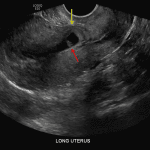

- Scar in the anterior lower uterine segment, likely related to prior C-section

- Intrauterine gestational sac within the lower uterine segment scar with very little tissue overlying the anterior margin of the gestational sac

- Mean sac diameter is 12 mm

- A fetal pole is present with crown-rump length measuring 8 mm

- Cardiac contractions are present with heart rate measured at 125 beats/minute

- Small subchorionic hemorrhage

C-section scar ectopic pregnancy

Single live gestation with gestational sac located in a scar in the anterior wall of the lower uterine segment, concerning for a C-section scar ectopic. Recommend obstetric evaluation. Gestational age is estimated at 6 weeks, 5 days by crown-rump length.